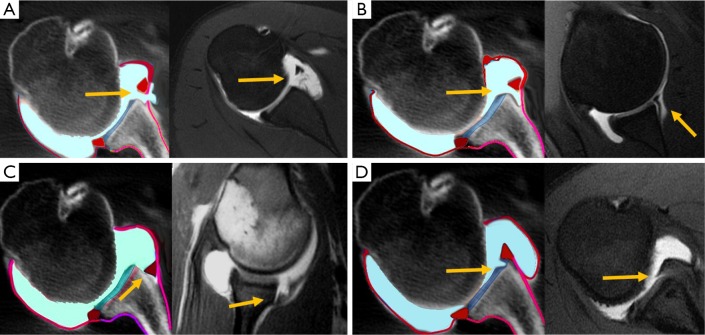

Hill-Sachs lesion occurs simultaneously with glenoid bone lesion in up to 62% of patients with glenohumeral instability (21). These combined injuries have been called bipolar bone lesions (22). Large humeral head Hill-Sachs lesions may cause engagement of the defect with the anterior labrum even after anterior glenoid reconstruction and, therefore, are indication for surgical repair (18). The prevalence of engaging Hill-Sachs lesion is about 7% (22). Typically, an engaging Hill-Sachs has an oblique long axis in neutral shoulder position that become parallel to the anterior edge in ABER position (abduction of 90° and external rotation of more than 30°). When the lesion has a vertical long axis in neutral shoulder position, it runs more diagonally with regard the anterior glenoid in ABER position, and have no tendency to engage (23) (Figure 5). It is also important the theory of glenoid track, defined as the contact area of the posterosuperior humeral head with the glenoid when the arm is raised in ABER position. The width of the glenoid track has been reported to be around 83–85% of the glenoid width (22). If the medial border of a Hill-Sachs lesion is lateral to the glenoid track, there is bone support adjacent to the Hill-Sachs lesion and the lesion is considered “on track” and will not engage; if the medial border of the Hill-Sachs lesion overpasses the glenoid track, there is no humeral bone support enough and the lesion is considered “off track” and will engage (22) (Figure 6).

Figure 5.

Engaging Hill Sachs lesion. (A) Hill-Sachs lesions obliquely oriented on neutral view become parallel to anterior labral rim in ABER position and tend to engage (B); (C) Hill Sachs lesions vertically oriented on neutral view become more diagonally oriented to anterior labral rim in ABER position and have lower tendency to engage (B).